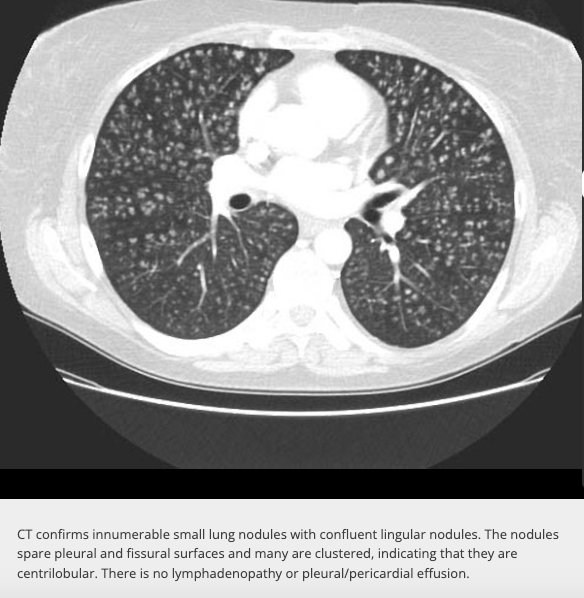

Centrilobular nodules

Differentials

(think inhalational)

Where are they located?

Located usually 3-5mm away from pleural surface and fisures. Within secondary pulmonary nodule. Can be any size or even ground glass. Distribution of most important.

1. Bronchiolitis due to infection (TB and MAI windermere)

2. Hypersensivity pneumonitis

3. Endobronchial spread of a lung tumour

Also think silicosis (inhalational)